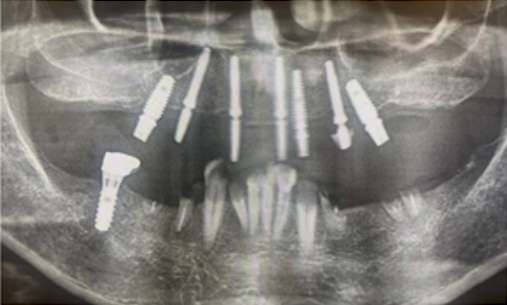

CTで確認すると骨量が充分にあるのですが細くて短いインプラントが7本入っている状態でした。オールオン4治療には必須の角度補正のSRAアバットメント(別名マルチユニットアバットメント)も装着されていない状態で偽物オールオン4というよりもオールオン7です。被せものはわずか3年で真っ二つに割れてしまったとのこと。下の歯の治療も放置されていました。

インプラント埋入後のレントゲン画像